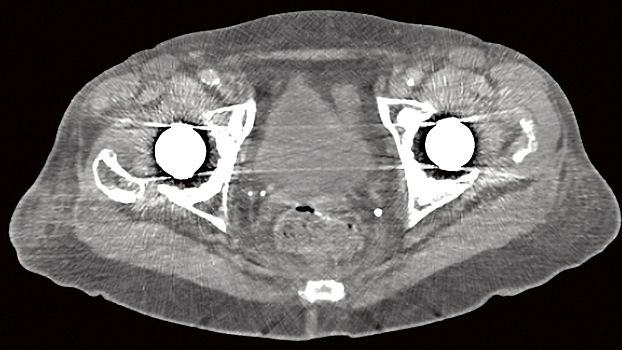

Клинические изображения

SOMATOM go.Up - компьютерный томограф для проведения рутинных и целевых осмотров, лучевой терапии и ангиографии. Система отличается инновационным дизайном рабочего места и полностью обновлённой концепцией сервиса, которая способствует снижению расходов по эксплуатации. Подходит для обследования головного мозга, легких, толстой кишки, сердца, сосудов. Вы можете заказать или купить со склада в наличии компьютерный томограф Siemens SOMATOM go.Up по выгодной цене, от надежного официального дистрибьютора "МСТ", с бесплатной доставкой в любой город по всей России.

Позволяет выполнять сканирование с низкой лучевой нагрузкой, что очень важно для оптимальной заботы о пациенте. SOMATOM go.Up выполняет сканирование больших диапазонов за одну задержку дыхания с высоким пространственным разрешением.

SOMATOM go.Up позволяет проводить высококачественные ангиографические исследования сосудов с хорошим контрастным усилением, субмиллиметровыми срезами и точной синхронизацией по времени.